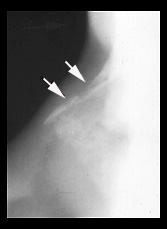

ABDOMINAL LYMPHADENOPATHY SPLEEN & LIVER GRANULOMAS

There are multiple enlarged paraaortic, paracaval, and porta hepatis lymph nodes (arrows).